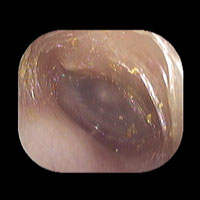

右急性中耳炎(中等症)

鼓膜がやや赤くなっています。鼓膜の奥に膿が透けて見えています。鼓膜の腫れはありません。抗生剤の内服で鼓膜切開を行わずに16日目で治りました。

14日目